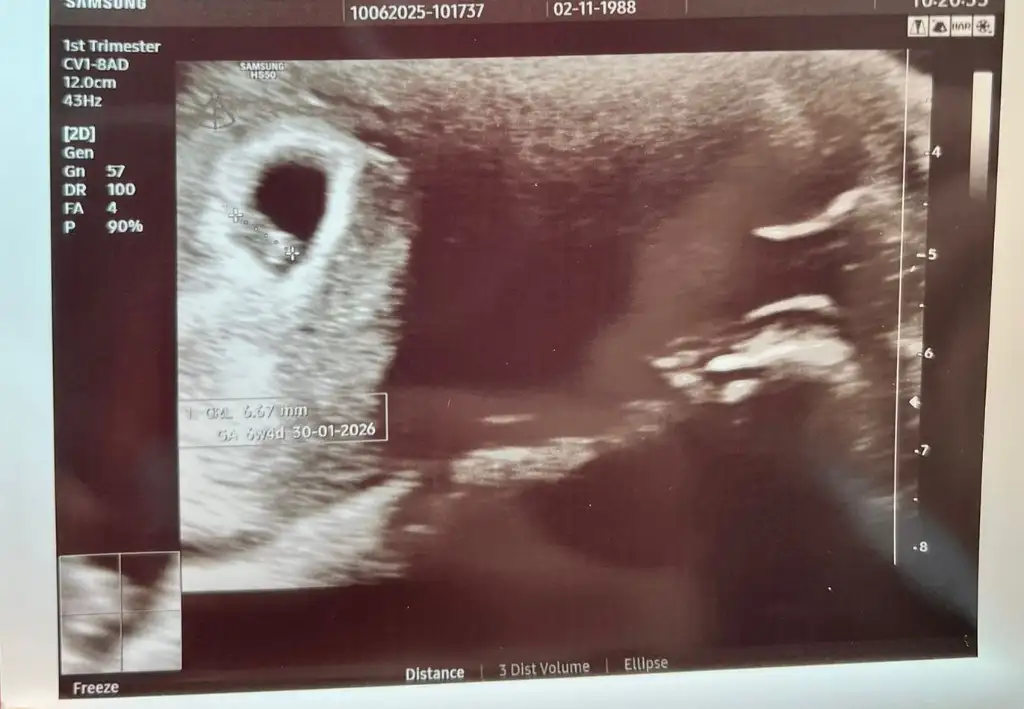

ErkekKızlar 6 haftalık ultrason görüntüsü. Ultrasın görüntüsünden cinsiyet tahmini yapanlar varmış. Bi bakabilir misiniz rica etsem

Erkek gibi geldi bana kesin olmamakla beraber. Sağlıkla gelsin inşallahKızlar 6 haftalık ultrason görüntüsü. Ultrasın görüntüsünden cinsiyet tahmini yapanlar varmış. Bi bakabilir misiniz rica etsem

Neye bakıyorsunuz tam olarak ben anlamıyorum da

Ben kese şekli fasulye gibiyse erkek yuvarlaksa kız diye okudumNeye bakıyorsunuz tam olarak ben anlamıyorum da